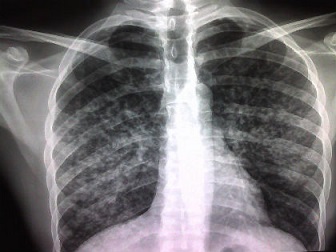

And of more immediate concern is they absolutely wish to keep Tuberculosis (TB) out of Australia. This is a nasty, debilitating lung infection which can lead to deaths if untreated. It's endemic in the Philippines and common amongst the poorer folk. Fortunately it responds well to treatment, but it always comes as a shock to those who get it. No one ever says “Yes, I thought I might have had it!” It’s not so obvious, as everyone has a few coughs from time to time. And it can be a crafty little critter when it comes to xrays too.

And there are no blood tests. The only way is looking at xrays with an experienced eye and identifying lesions in the lungs. And this is not always easy or obvious.

I can share our experience. We’ve taken in kids here who have had it, and we’ve had them treated successfully. Three to date, and all in excellent health now. I was with them when they were diagnosed, and I can assure you it wasn’t straight forward. Our family doctor has maybe 30 years of experience, and it generally took several xrays sometimes from different angles before they were certain.

And we had one case where one child had a lung infection which meant the lungs were congested already. Couldn’t see a thing! Seeing as her sister had been diagnosed with TB already, the doc took a punt and put her on TB medication anyway just in case. A later chest xray a month later showed there were no lesions, but it was considered not worth taking such a risk.